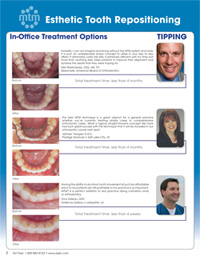

Esthetic Tooth Repositioning with Essix

Patient 1

Patient 2